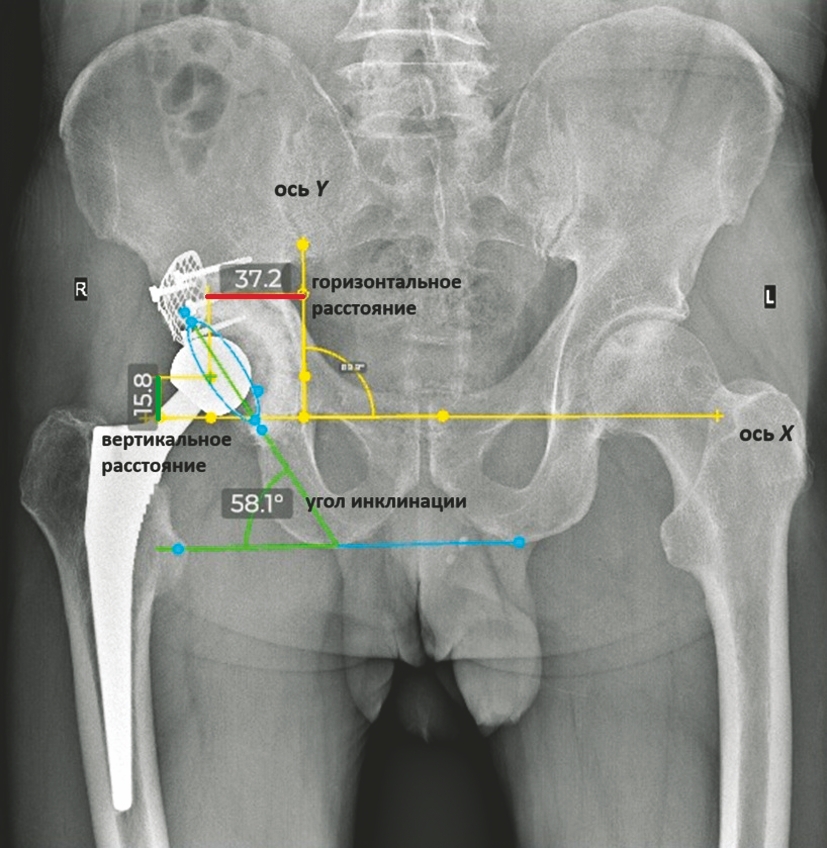

To assess changes in the position of the center of rotation of the acetabular component over time, a horizontal reference line (X-axis) was drawn through the inferior margin of the “teardrop” figure on both hips. A perpendicular line (Y-axis) was then drawn from the lateral edge of the “teardrop” on the operated side. Horizontal and vertical distances from the center of the prosthetic femoral head were measured by projecting perpendiculars from the head center to the X and Y axes [26]. Additionally, we measured the inclination angle of the acetabular component relative to the X-axis and its anteversion (Figure 1).

Figure 1. Scheme of acetabular component displacement measurements

The magnitude of acetabular component displacement was determined by calculating the difference between the initial and final positions of the center of rotation along the X and Y axes. Similarly, changes in inclination and anteversion angles were assessed. Calibration of radiographic images was performed using DICOM files, and all measurements were conducted with the BonaPlanner 2D software, utilizing the “postoperative control” function.